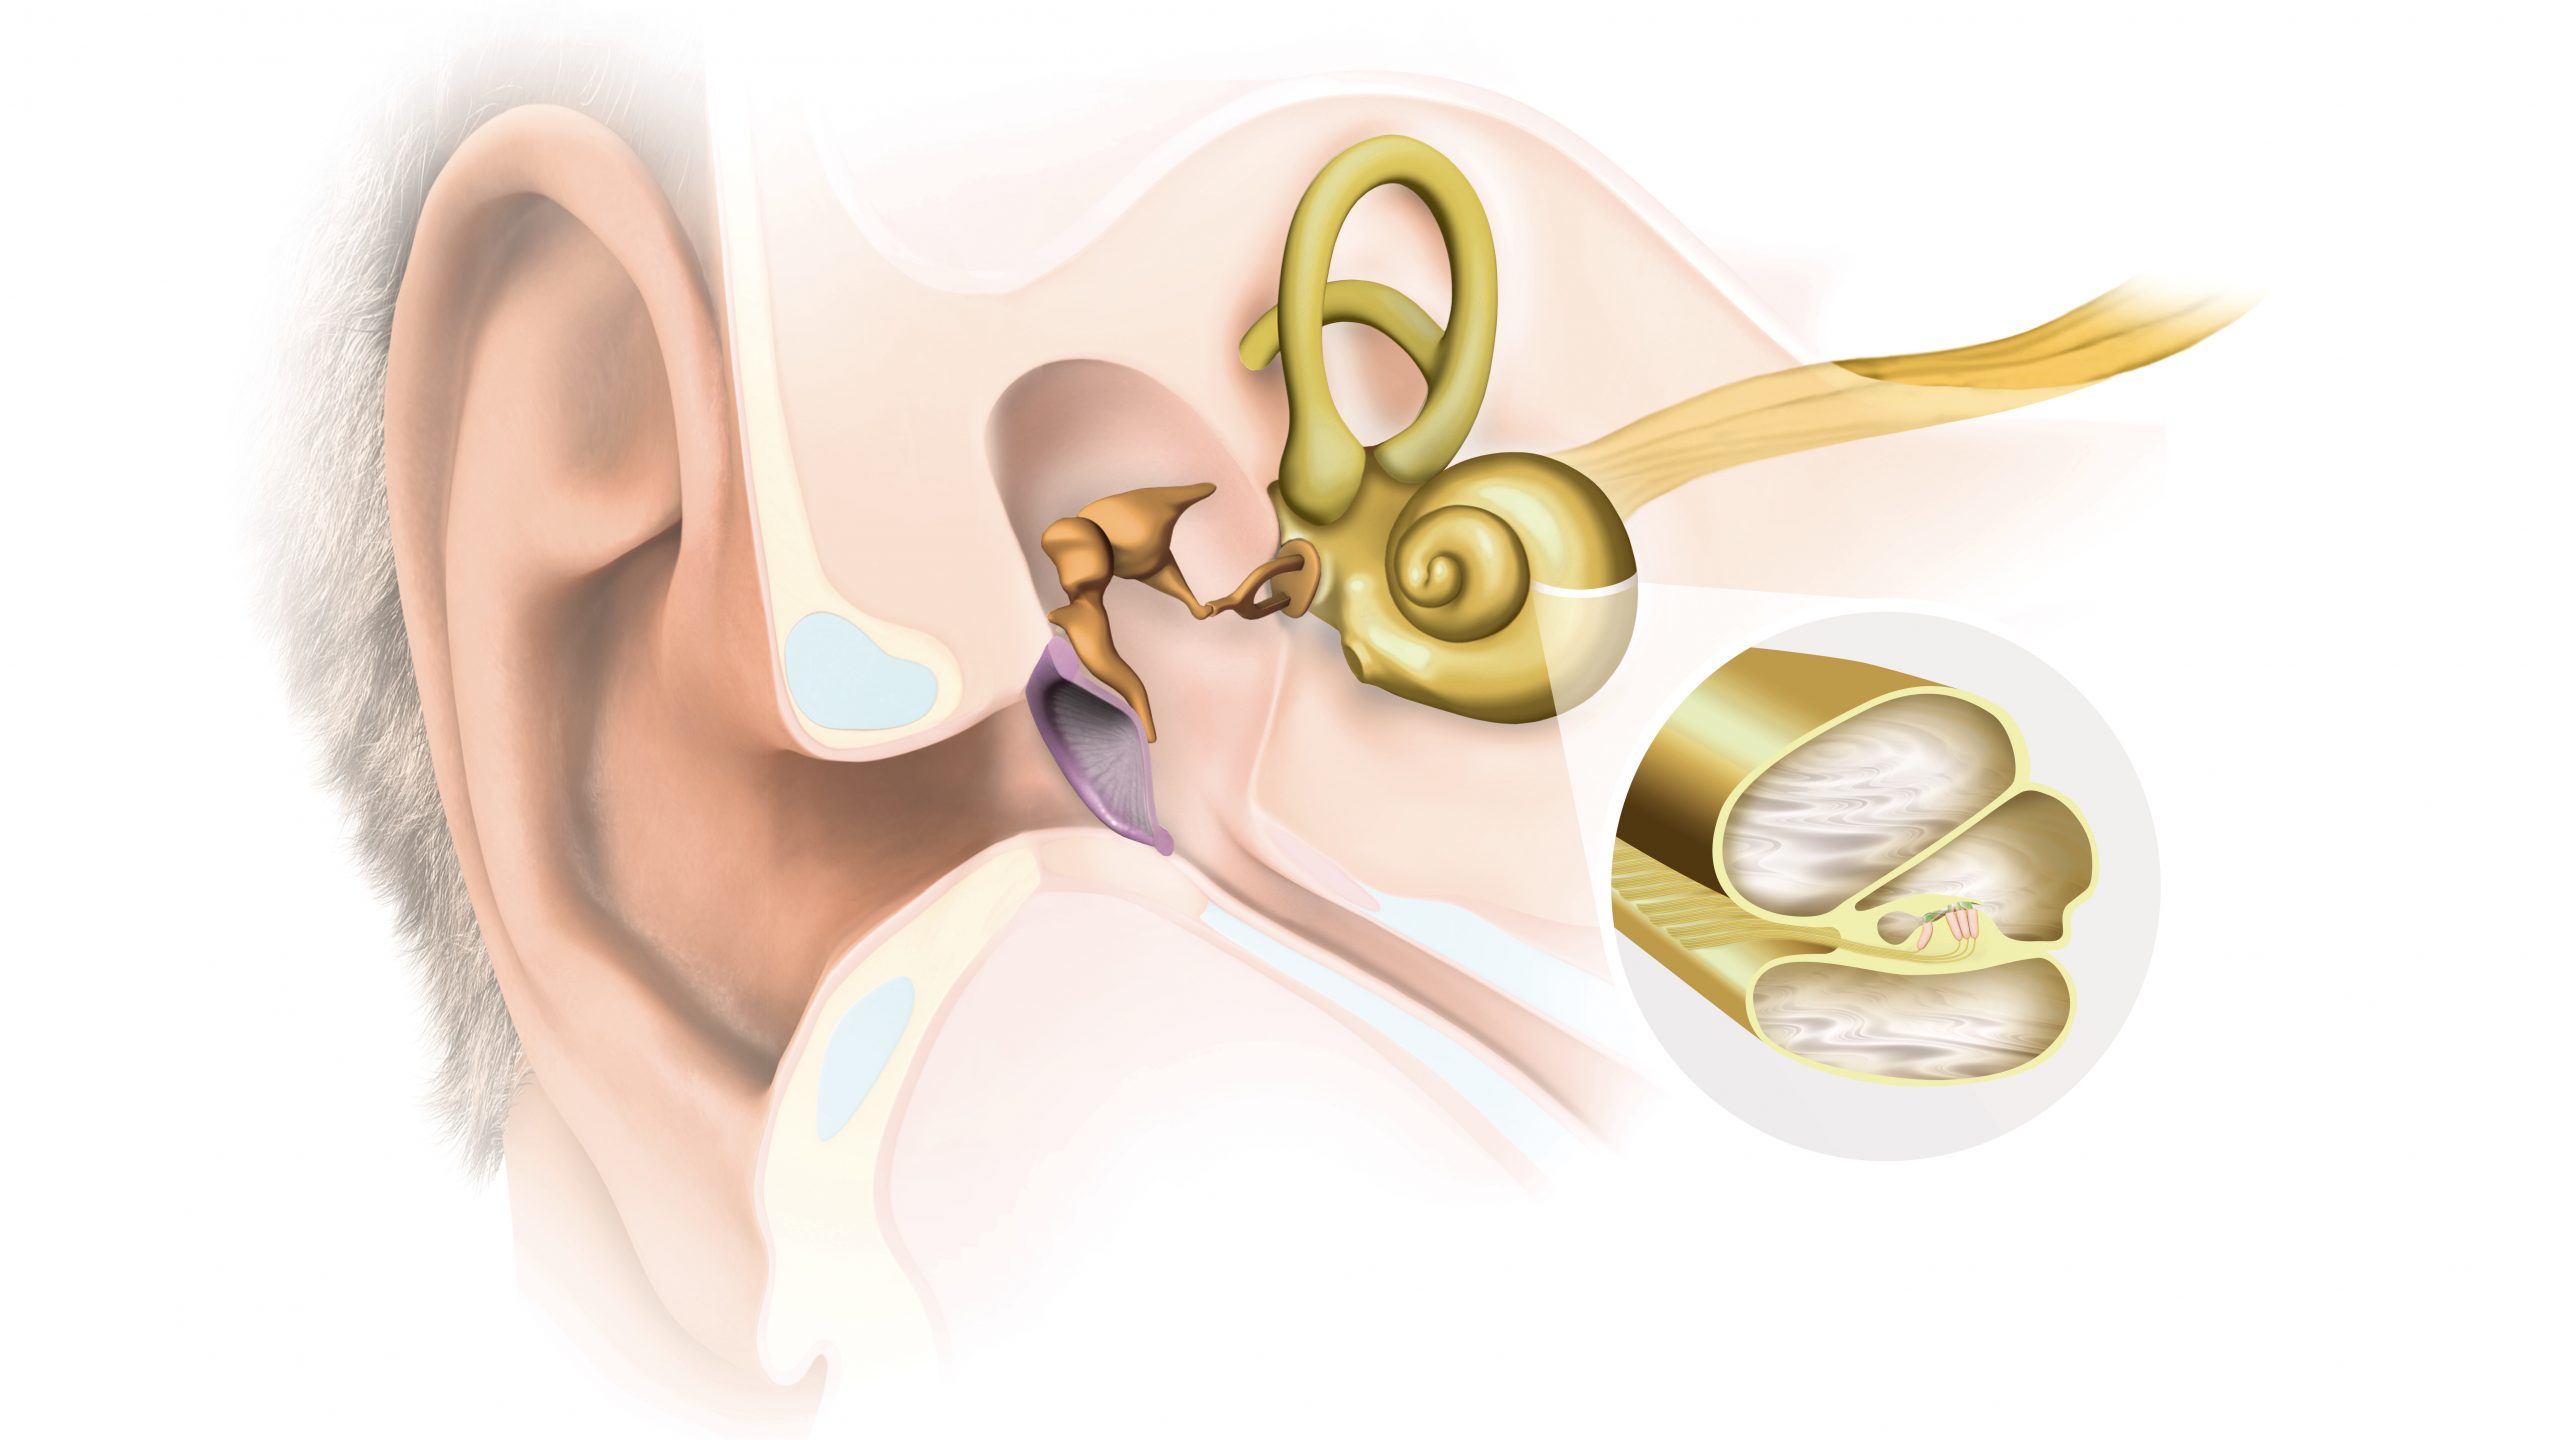

Современные слуховые аппараты при сенсоневральной тугоухости